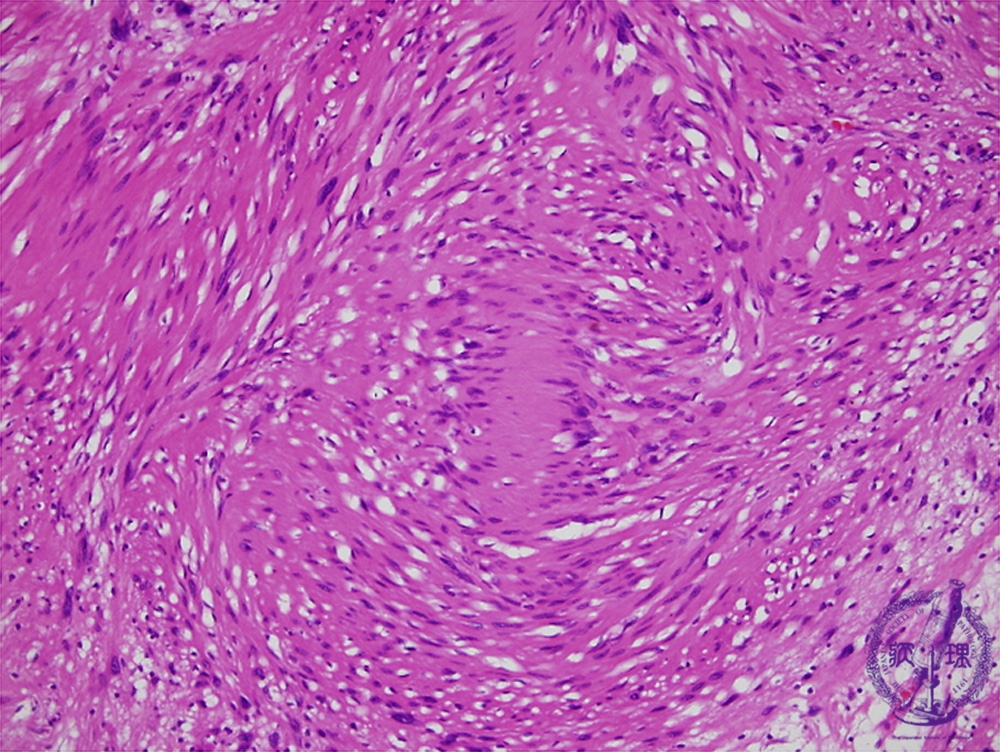

Microscopic findings (H.E. high power view): In Antoni A area, ball-like fibrous bundles with bipolar nuclear palisading, termed Verocay bodies, are also identified (red circle).

Click the image to see the enlarged image.